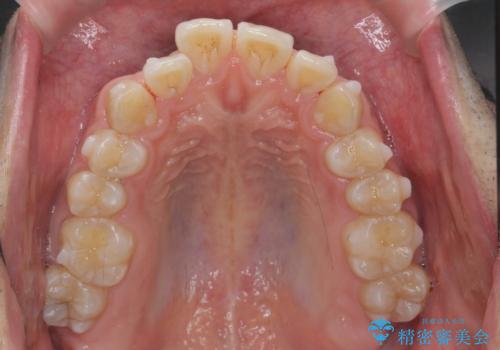

マウスピース矯正で前歯の角度、ガタガタをきれいに

- 突き出た前歯の角度、歯ブラシのしづらい前歯のがたつきの改善を希望され来院されました。

4本の小臼歯を抜きワイヤー矯正治療、下顎前歯を1本抜去しマウスピース治療のメリットデメリットを検討・相談し、より歯を抜く本数の少ないマウスピース矯正を行うこととなりました。

下顎の前歯は1本だけ抜去せざるをえませんでしたが、4本の小臼歯抜去とマルチブラケット矯正を回避することができ、治療結果・過程に満足いただくことができました。